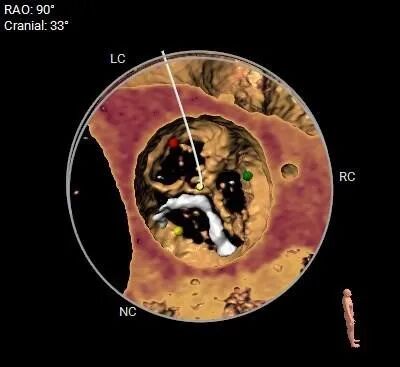

3D打印评估

术前3D打印评估主动脉根部

主动脉根部评估

瓣上多平面分析